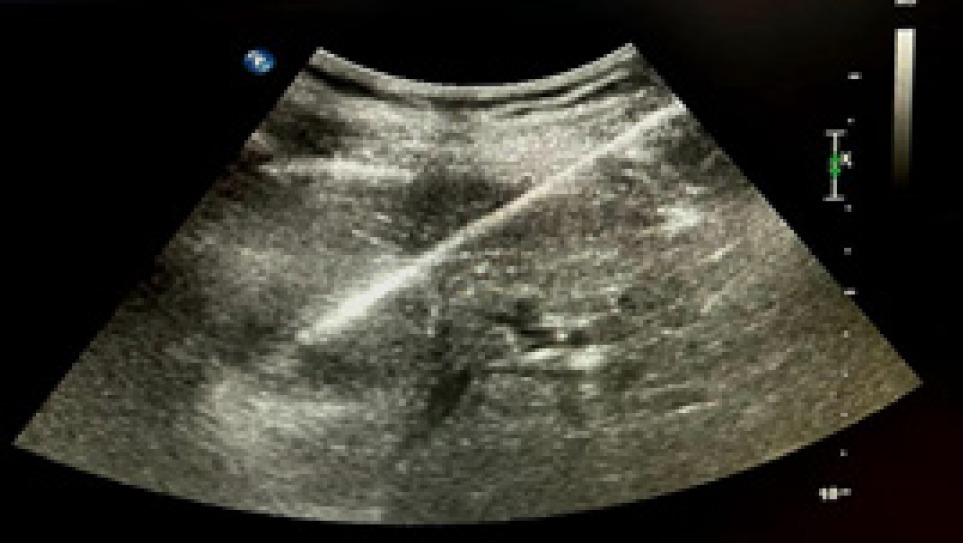

Twenty-eight patients underwent RFA for small renal masses and were followed-up for 3 years. Out of 28 patients, 20 were males (71.42%) and 8 were females (28.57%) (Table 1). The median age of the patients was 65.5 years (Range: 44). The median size of the lesions was 2.35 cm in the greatest dimension (Range: 3). The median estimated glomerular filtration rate (eGFR) before the procedure was 87.6 mL/min/1.73m2 (Range: 153.7) and the median eGFR after the procedure was 64.55 mL/min/1.73m2 (Range: 155), which did not show any significant change in renal function after ablation (P-value: 0.29). A biopsy was done before the procedure to have a histological confirmation (Figure 1). Out of 28 patients, 26 patients were found to have clear-cell carcinoma and 2 patients had papillary carcinoma of the kidney. Two patients had postoperative complications forming hematoma post-procedure, which was managed by tight compression over the skin and oral antibiotics. There was no other associated complication or toxicity. Two patients out of 28 had VHL association. The mean time of the procedure was 10.07 min. The mean duration of stay in the hospital was 1 day.

Figure 1: Ultrasound image of renal biopsy before ablation.